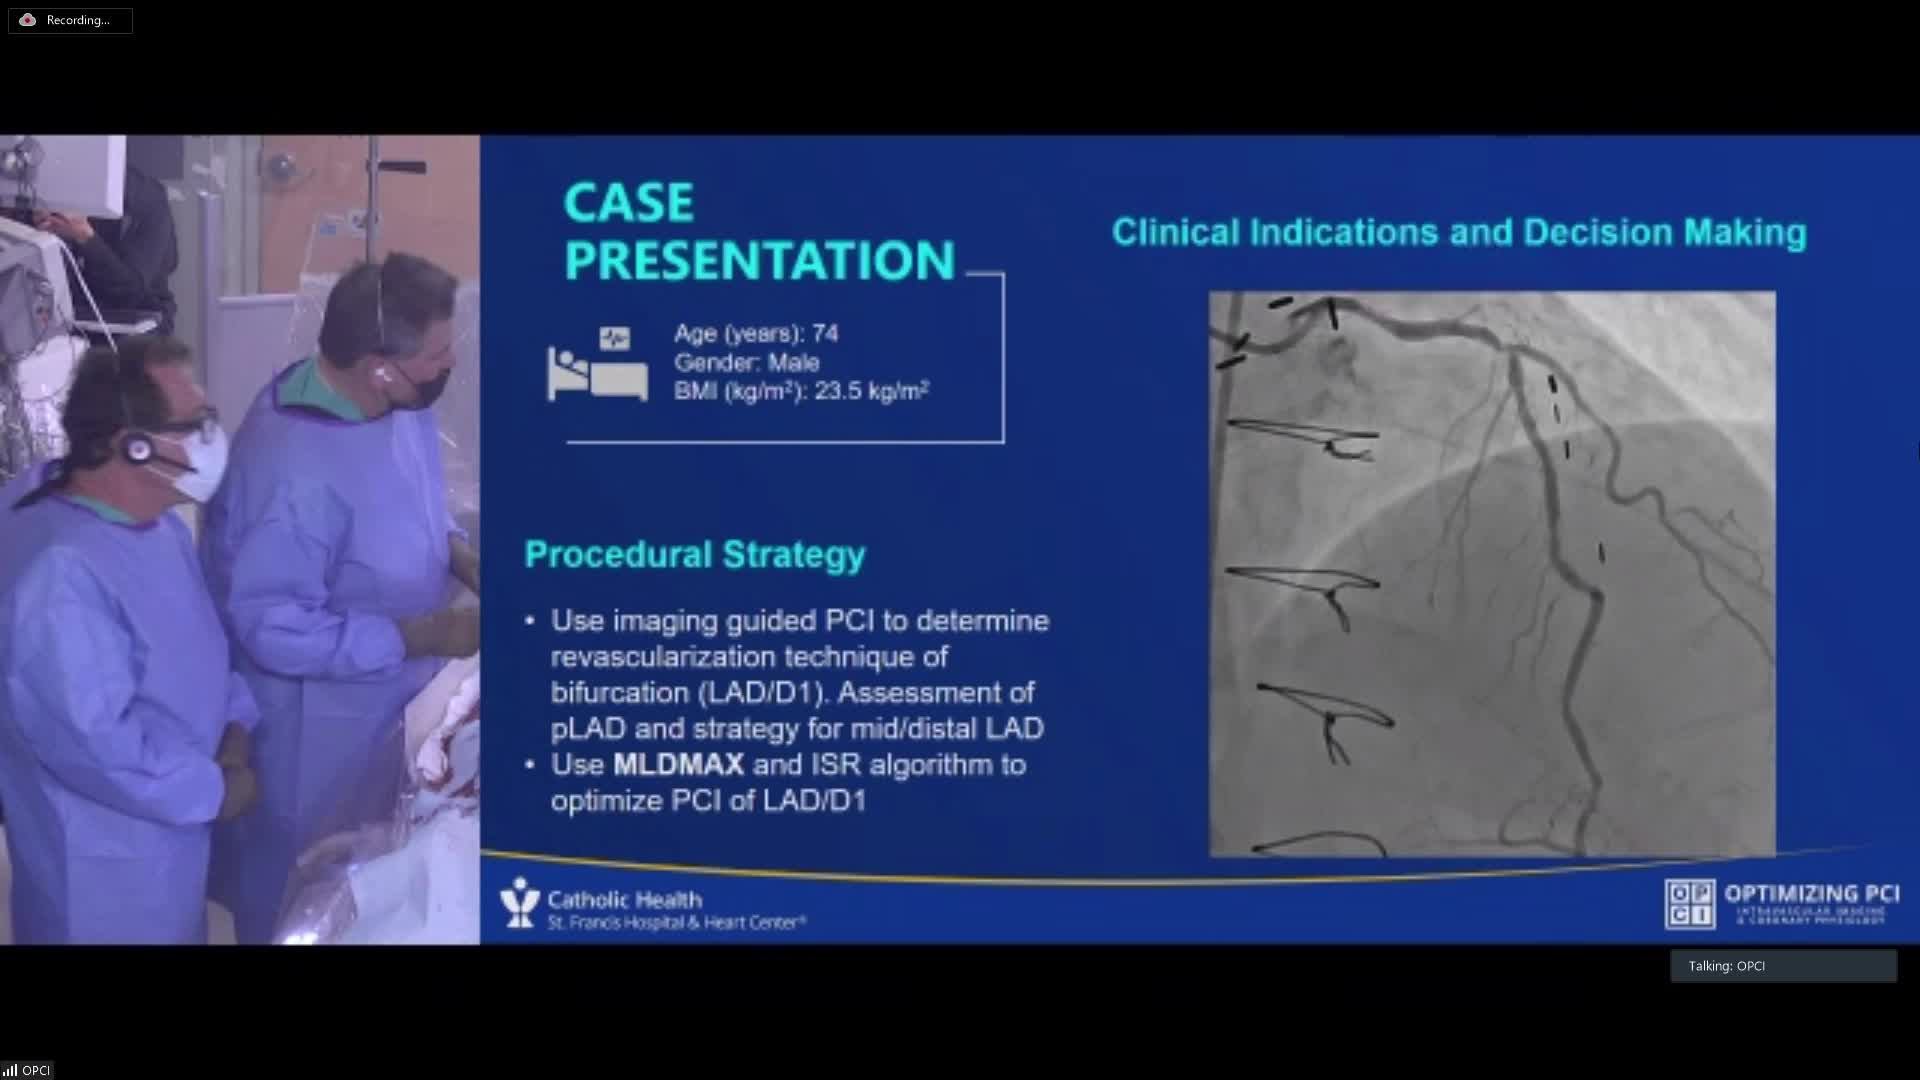

The integrated use of physiology and imaging is transforming the treatment of complex bifurcation disease. We explore...